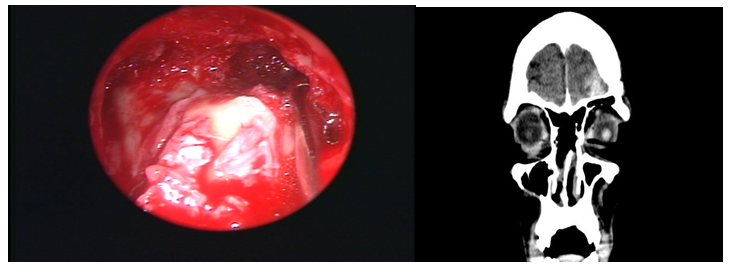

In three, the modified Lothrop technique was used to expand the margins of oncology resection due to malignant tumors that that compromised the recess and the frontal sinus. In one it was combined with an external approach. We used the optical neuronavigation system in three cases (Figure 3 & Figure 4). In 12 patients, the sinus was approached through its ostiums (inside-out), and in 4 cases the frontal sinus was drained starting from the frontal recess floor in the midline (ouside-in). One patient had a cerebrospinal fluid fistula as a complication, which was detected and repaired with free grafts with multilayer technique in the same surgical time. One patient had unilateral frontal headaches 5 years after the Lothrop modified technique surgery. A unilateral blockage of frontal drainage was identified by mucosal hyperplasia caused by its allergic fungal sinuistis (Figure 5). It was operated again by transnasal route and the sinus was permeabilized. Another patient had a complete obliteration of the frontal drainage 1 year after surgery. It was operated again with modified Lothrop technique and it was possible to wide the frontal recess drainage pathway. The other patients had a permeable frontal drainage and were asymptomatic during the average follow-up time of 3.5years. The permeability of the frontal drainage obtained with modified Lothrop technique was 87.50% (14/16), and with rescue endonasal surgery, the permeability was 100%.

Figure 3 Epidermoid carcinoma of the frontal sinus. External approach+modified Lothrop procedure.

Figure 4 Undifferentiated carcinoma: Modified Lothrop procedure.